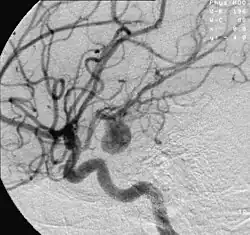

![]() | |

| Angiography of an aneurysm in a brain artery. The aneurysm is the large bulge in the center of the image. | |

Diagnosis of a ruptured cerebral aneurysm is commonly made by finding signs of subarachnoid hemorrhage on a computed tomography (CT) scan. If the CT scan is negative but a ruptured aneurysm is still suspected based on clinical findings, a lumbar puncture can be performed to detect blood in the cerebrospinal fluid. Computed tomography angiography (CTA) is an alternative to traditional angiography and can be performed without the need for arterial catheterization. This test combines a regular CT scan with a contrast dye injected into a vein. Once the dye is injected into a vein, it travels to the cerebral arteries, and images are created using a CT scan. These images show exactly how blood flows into the brain arteries.[39]

There are currently two treatment options for brain aneurysms: surgical clipping or endovascular coiling. There is currently debate in the medical literature about which treatment is most appropriate given particular situations.[41]

Endovascular coiling was introduced by Italian neurosurgeon Guido Guglielmi at UCLA in 1989. It consists of passing a catheter into the femoral artery in the groin, through the aorta, into the brain arteries, and finally into the aneurysm itself. Platinum coils initiate a clotting reaction within the aneurysm that, if successful, fills the aneurysm dome and prevents its rupture.[42] A flow diverter can be used, but risks complications.[43]